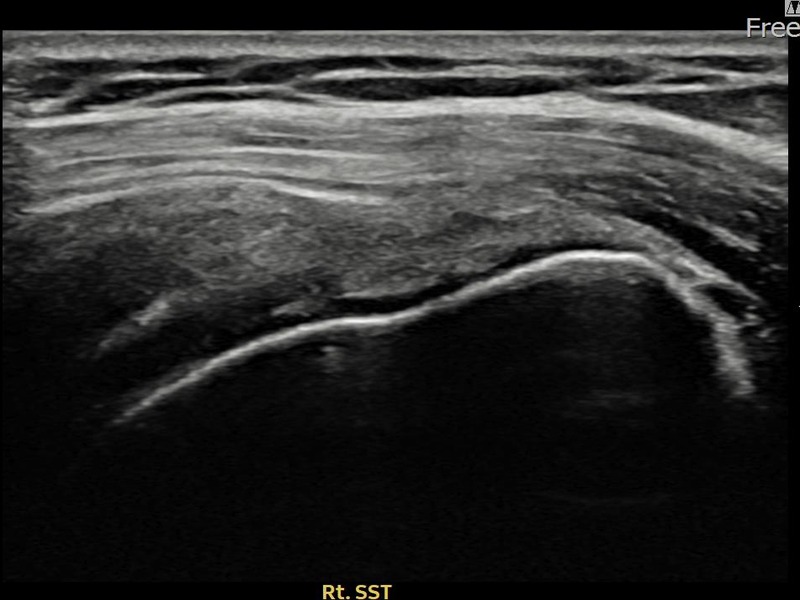

최ㅇㅇ님 · 우측 극상근건 관절면측 부분파열

우측 어깨 통증으로 수면과 일상 동작이 어려워 내원하셨습니다. 초음파 유도 하 축소봉합술 후 힘줄 연속성이 회복되었습니다.

상세 보기 →